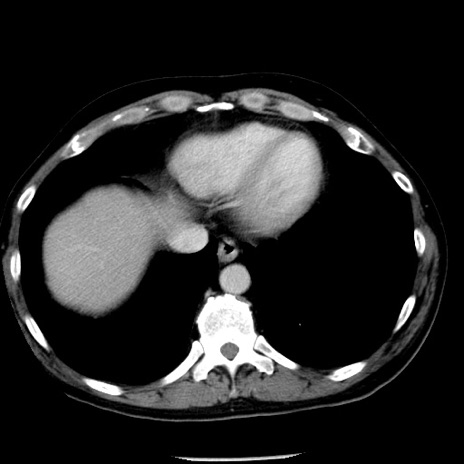

症例29(横断像)

【症例】40歳代男性

【現病歴】2日前から胃痛あり。徐々に周期的な激痛に変化した。本日になっても激痛があるため受診。

【身体所見】意識清明、BT 38-39℃台あり、腹部:膨満、やや硬、右下腹部に圧痛あり。

【データ】WBC 8500、CRP 23.26